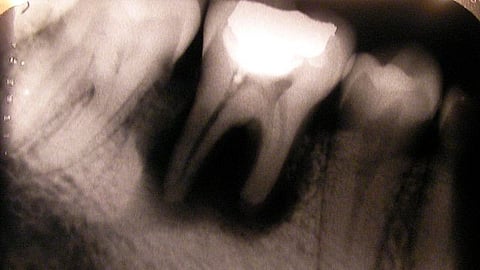

Radiographic features:

Outline of the lesion: The lesion appears as a round-to-oval radiolucent enlargement of pulp space. There will be distortion in the outline of the root canal.